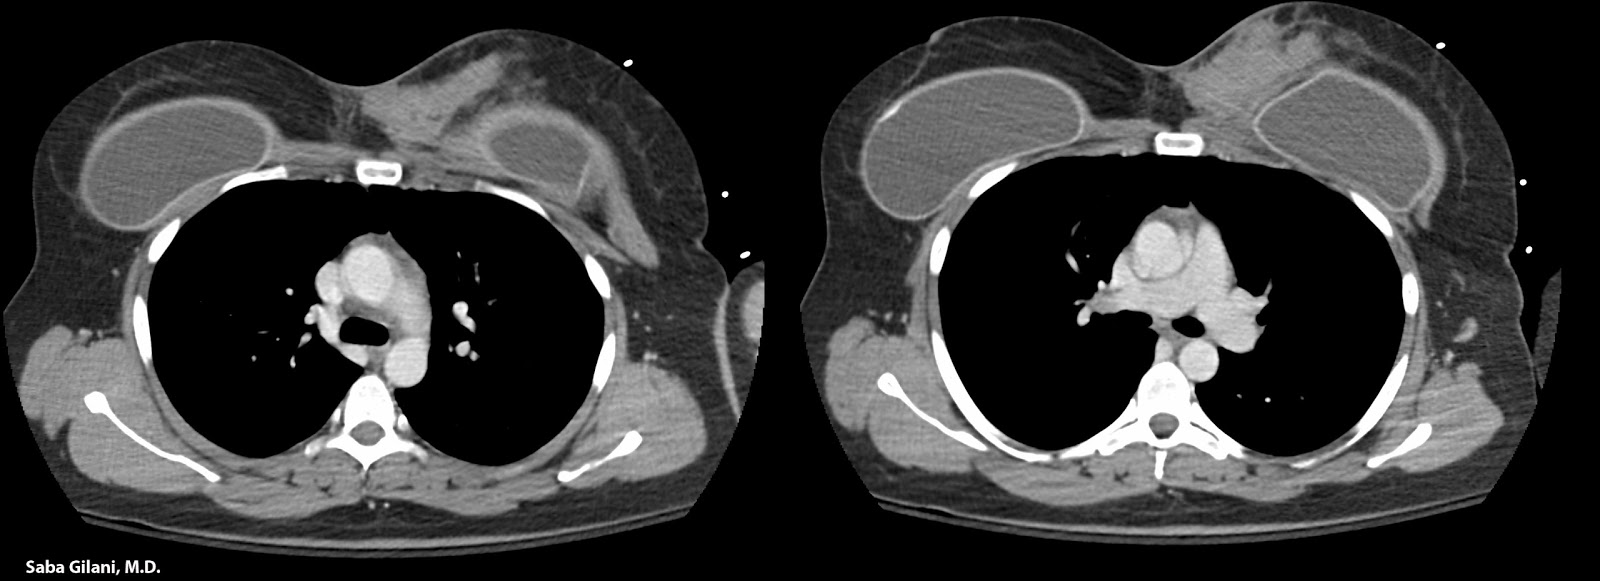

Заподозрить наличие патологии врач может уже при простом визуальном осмотре и пальпации. Для подтверждения диагноза применяются аппаратные способы исследования:

- МРТ (магнитно-резонансная томография). Наиболее эффективный метод, дающий полную клиническую картину и имеющий мало противопоказаний.

- УЗИ (ультразвуковое исследование). С его помощью можно точно определить размер и местоположение серомы. Применяется для диагностики осложнения на ранних стадиях.

- Рентгеновская маммография. Позволяет отследить состояние прооперированной области в целом и быстро обнаружить очаги скопления жидкости в тканях.